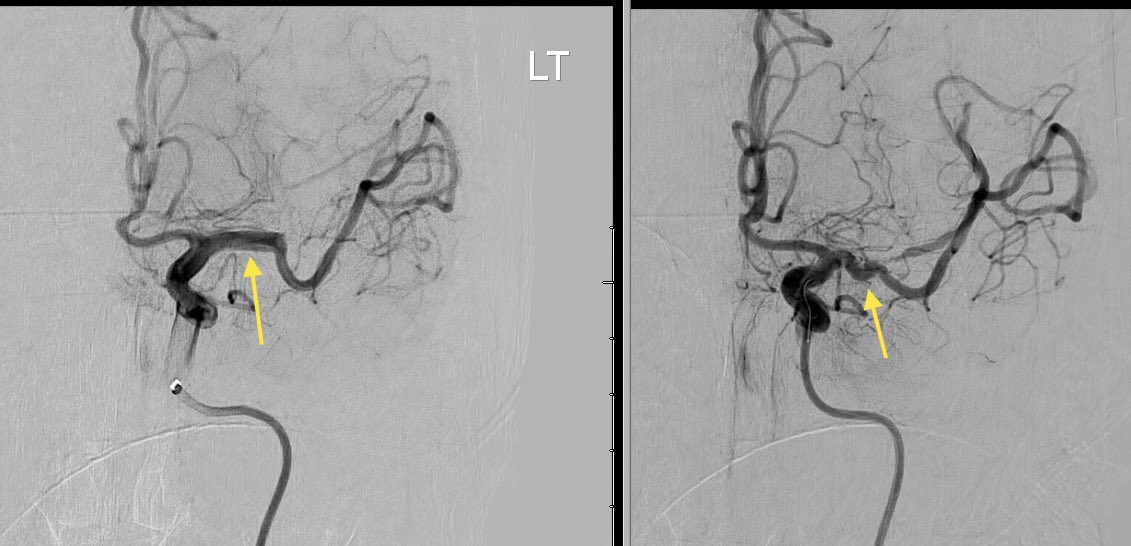

@YNIScommittee @andrewyu8 @RaghavMattay @DoctorSiz @DrJessicaCampos Agree that this is left cervical ICA occlusion with collateralization from the left vertebral artery segmental branches, which appear to be musculospinal collaterals feeding back into the ICA

This is a left vertebral artery angiogram in a middle aged patient presenting with transient aphasia. Can you guess what is going on here? What are the vessels marked by yellow arrows? @andrewyu8 @CharlesBeaman @RaghavMattay @DoctorSiz @DrJessicaCampos